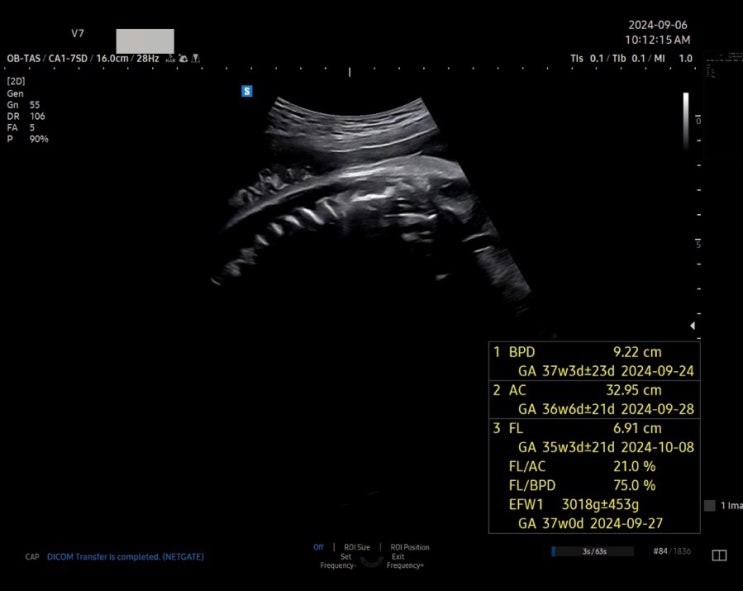

임신 37주 임당재검통과 산모 간식 박순석찹쌀떡 추천

안녕하세요. 지번주 산부인과 정기검진을 다녀오고 갈릭이가 생각보가 리 크고 있어서 열심히 식단 관리를 ...